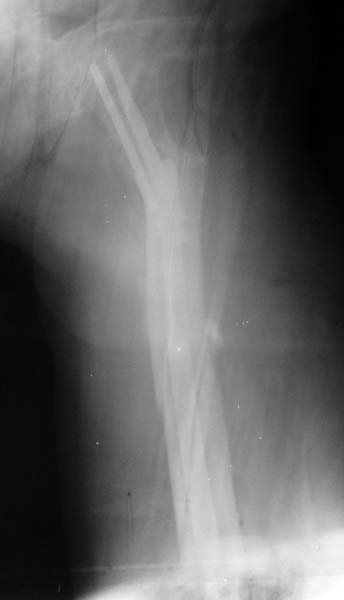

Уважаемые коллеги, на форуме был представлен случай перелома шейки и диафиза бедра, где после БИОС наступил варус шейки и винты упирались в крышу сустава.

Форумом было рекомендовано пересинтезировать. Мы пригласили нашего дорогого друга Челнокова А.Н., основоположника БИОС в нашем регионе, который несмотря на очень занятость, и дальность расстояния решил выручать коллег, и приехал к нам. Уже прошло 2 мес. после первой операции. Винты из шейки удалены, наложен дистрактор, произведена закрытая репозиция шейки, стержень ChM удален, произведен остеосинтез стержнем DePuy, шейка фиксирована, кроме стандартных двух винтов, еще одним винтом спереди стержня. рентген снимки прилагаются.

Имя     : forum lateral view.jpg